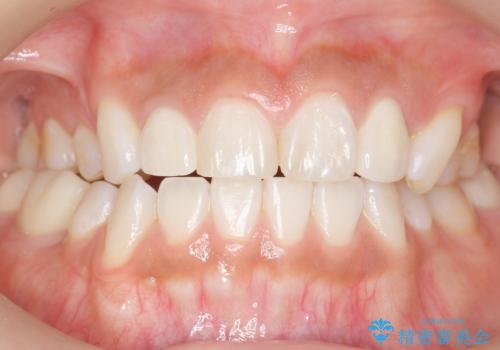

矯正せずに早く治したいという強いご希望により、セラミッククラウンによる補綴治療(上顎両側2の2本)を行いました。

- ¥396,000 (根管治療・土台×1本、仮歯・クラウン×2本) ※税込費用は治療当時の料金となります

天然歯のような自然な仕上がりに大変喜んで頂けました。

クラウンの種類:オールセラミッククラウン スペシャル